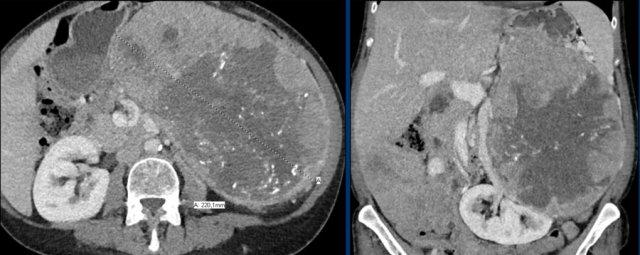

Hình ảnh cho thấy một tổn thương ngấm thuốc không đồng nhất, bờ tương đối rõ, kích thước 67 mm.

Sau phẫu thuật cắt bỏ, tổn thương được xác định là ung thư biểu mô vỏ thượng thận.

Hình ảnh cho thấy một tổn thương không xác định kích thước lớn với tỷ trọng không đồng nhất và vỏ vôi hóa một phần.

Sinh thiết cho thấy u cơ trơn tuyến thượng thận.

Tổn thương đã được phẫu thuật cắt bỏ.

Đây là tổn thương không xác định, ngấm thuốc không đồng nhất, bờ tương đối rõ.

Tổn thương được xác định là u tủy thượng thận (pheochromocytoma).

Tổn thương tuyến thượng thận ngấm thuốc mạnh kích thước 7 cm với các ổ nang nhỏ.

Tổn thương được phẫu thuật cắt bỏ do kích thước lớn và đặc điểm hình ảnh không xác định.

Kết quả mô bệnh học xác định đây là u tuyến (adenoma).